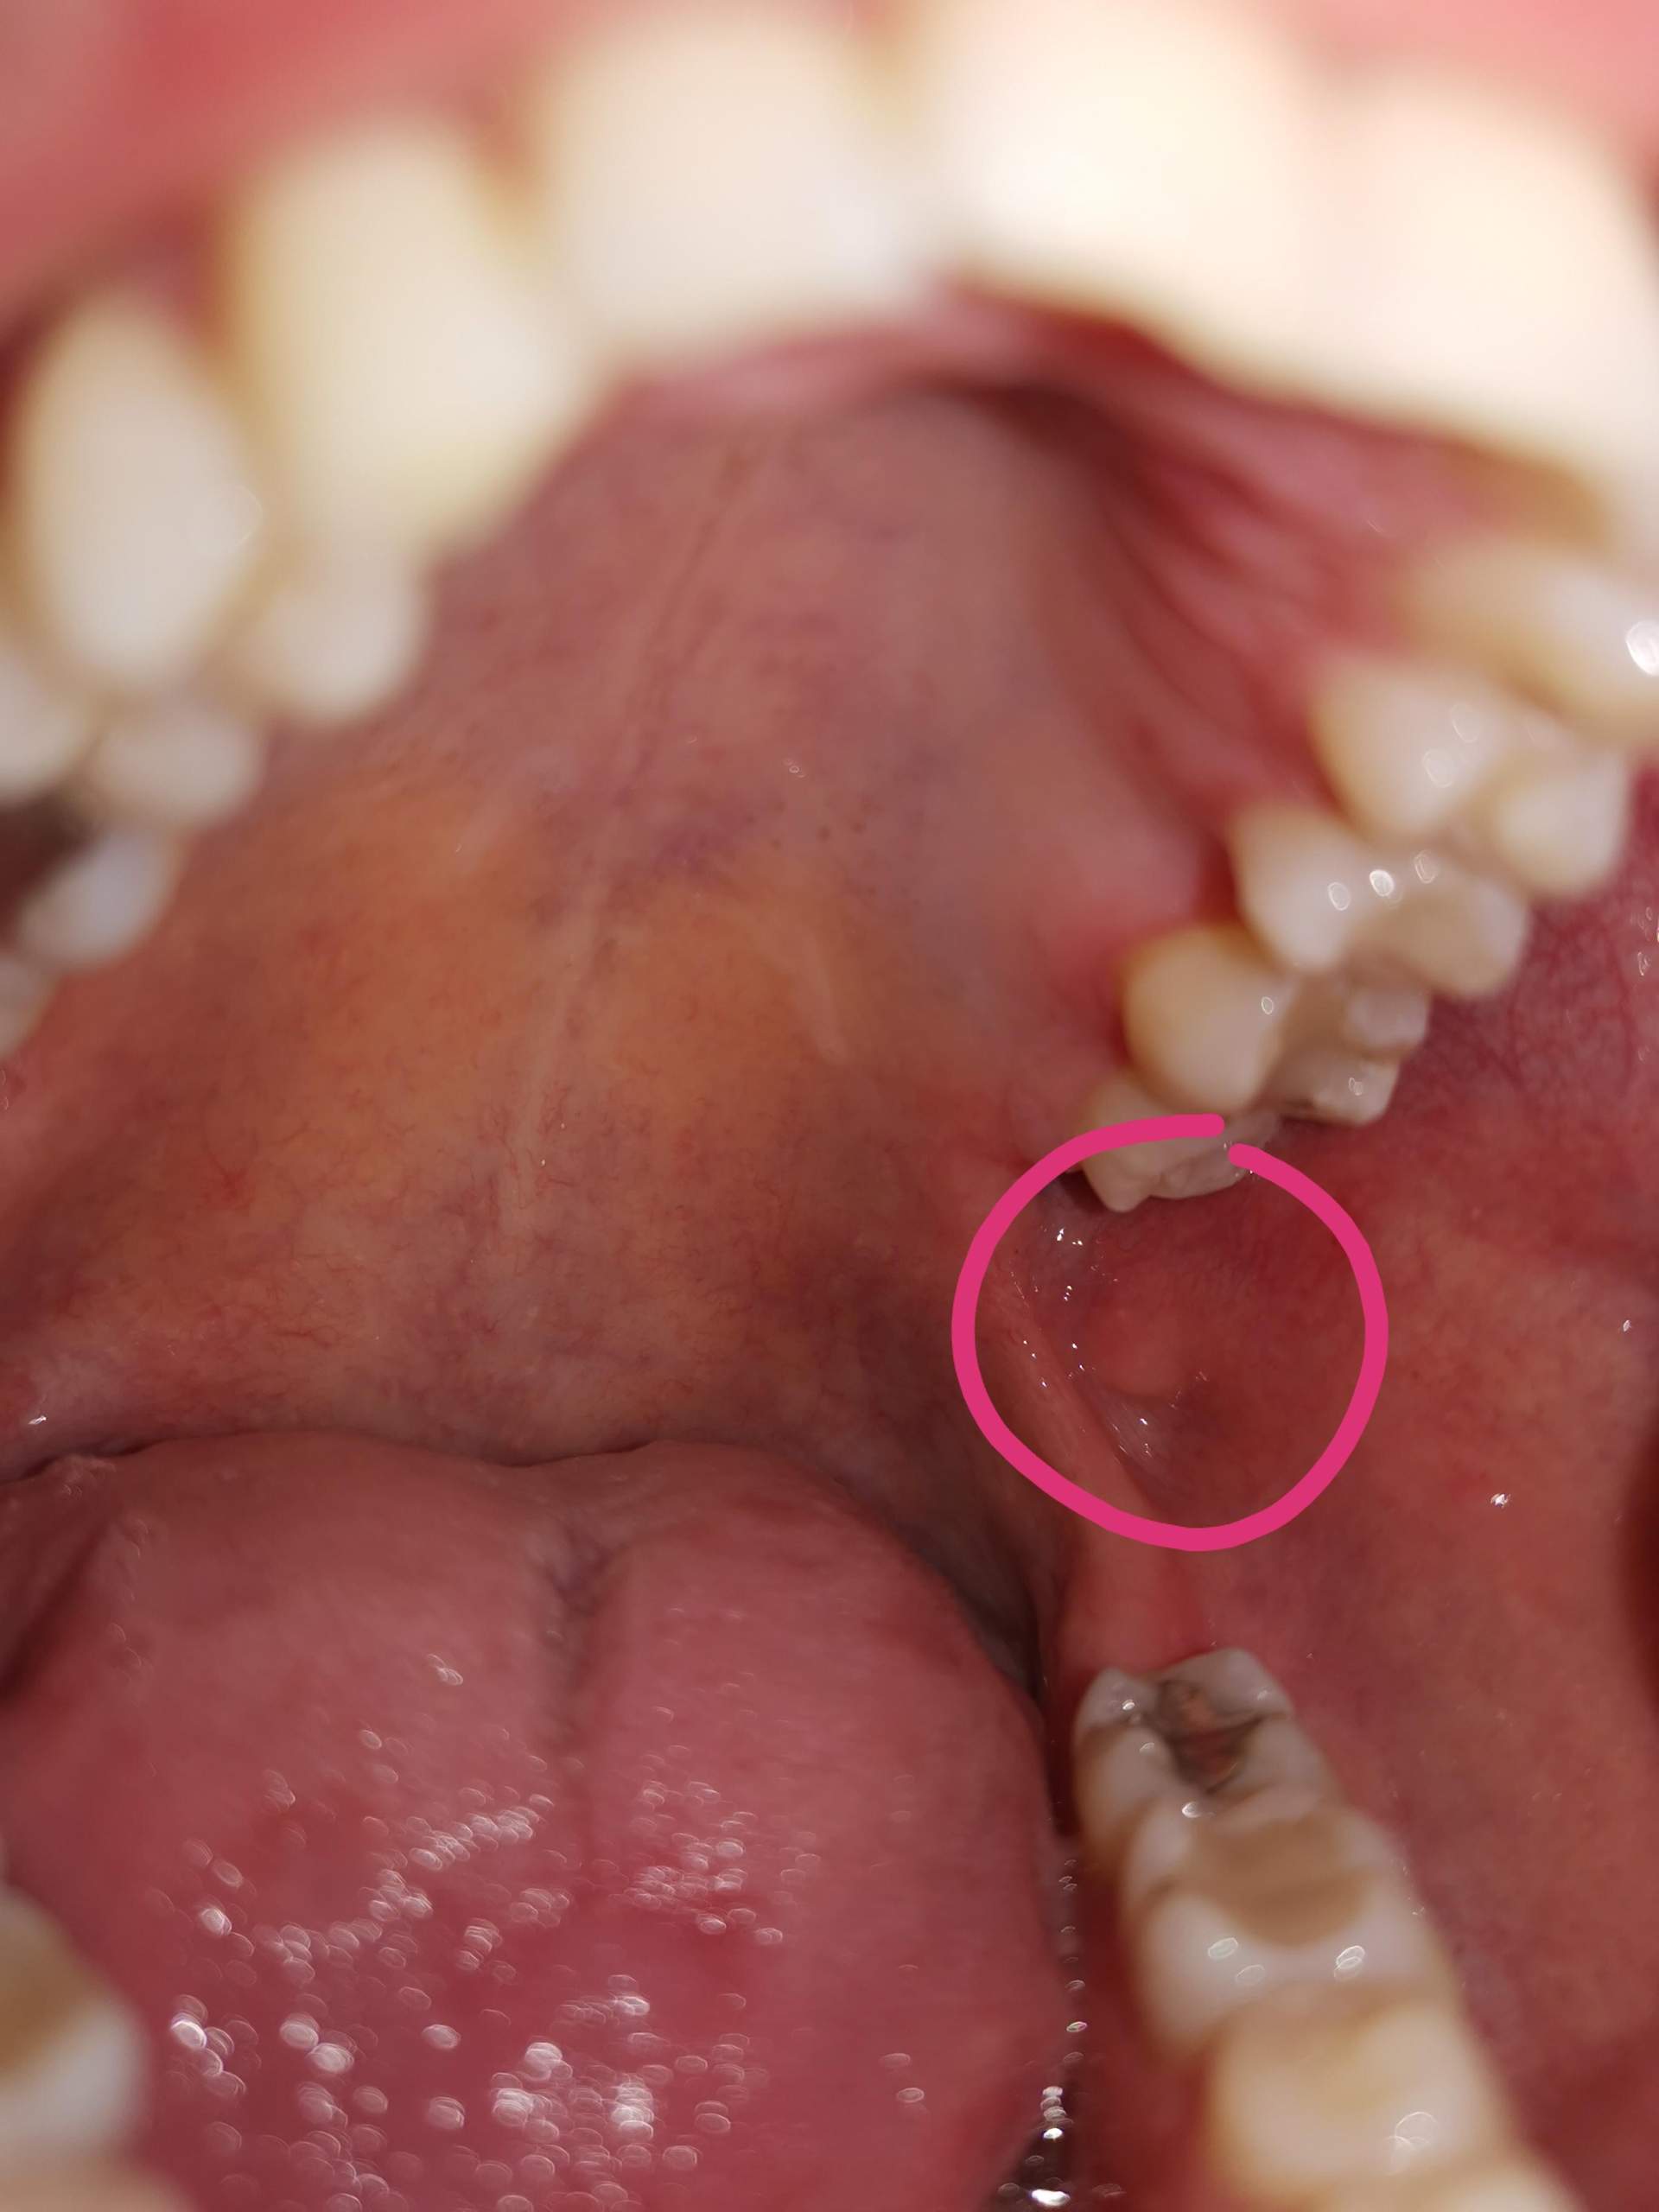

Tumor Im Mundraum? (Medizin, Mund, Rachen)

Tumor im Mundraum? (Medizin, Mund, Rachen) www.gesundheitsfrage.nettumor mundraum mund rachen